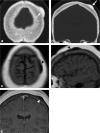

Calvarial lesions are often asymptomatic and are usually discovered incidentally during computed tomography or magnetic resonance imaging of the brain. Calvarial lesions can be benign or malignant. Although the majority of skull lesions are benign, it is important to be familiar with their imaging characteristics and to recognise those with malignant features where more aggressive management is needed. Clinical information such as the age of the patient, as well as the patient's history is fundamental in making the correct diagnosis. In this article, we will review the imaging features of both common and uncommon calvarial lesions, as well as mimics of these lesions found in clinical practice. TEACHING POINTS: • Skull lesions are usually discovered incidentally; they can be benign or malignant. • Metastases are the most frequent cause of skull lesions. • Metastatic lesions are most commonly due to breast cancer in adults and neuroblastoma in children. • Multiple myeloma presents as the classic "punched out" lytic lesions on radiographs. • Eosinophilic granuloma is an osteolytic lesion with bevelled edges.